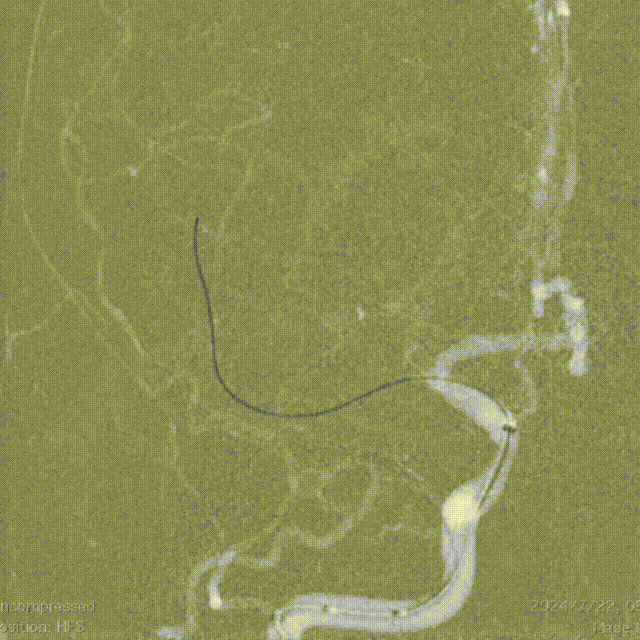

冒烟确定真腔,经21系列 Fastunnel®输送型球囊扩张导管释放Syphonet®取栓支架 4*30mm。

释放Syphonet®取栓支架 4*30mm后造影。

21系列 Fastunnel®输送型球囊扩张导管 1.75*10mm球囊到位。

Fastunnel®输送型球囊扩张导管 1.75*10mm缓慢扩张至命名压6atm。

Fastunnel®输送型球囊扩张导管 1.75*10mm扩张后造影。

回收Syphonet®取栓支架 4*30mm,留置神经微导丝,即刻造影,观察10分钟、15分钟。